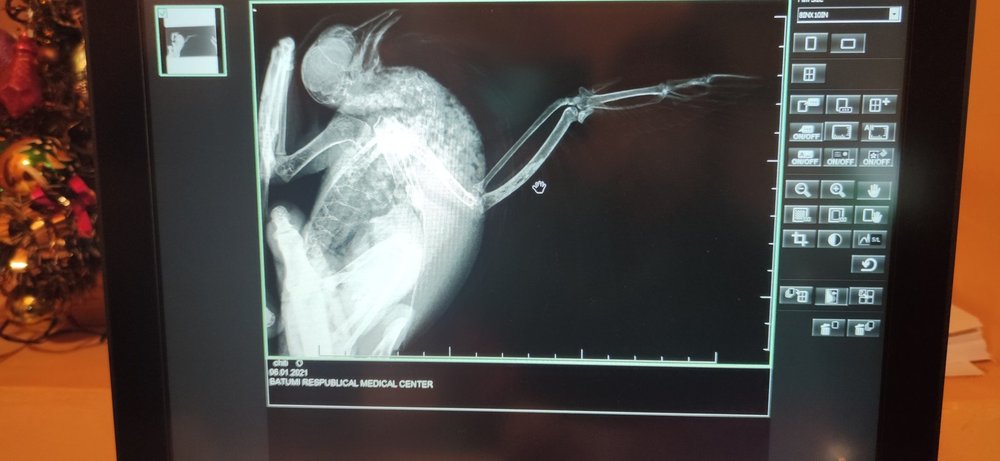

ksjsha Опубликовано 6 января, 2021 Автор #41 Опубликовано 6 января, 2021 (изменено) 42 минуты назад, ksjsha сказал: Ураааа,я такая реально счастливая?я договорилась за рентген в поликлинике,в ветклинике рентгена нету ? сейчас бегу за Гулей.Скажите,как именно мне его нужно делать и как Гулю дожить!? Я не уверена,что они знают?они же по людям. Вот так ,как на фото? Всех с рождеством! Я все сделала?не знаю радоваться или огорчаться?они говорят,что перелома нет. Я вот думаю,может я неправильно ее положила. Может плохо видно все ее косточки и суставы!? Что тогда с ней!?Ушиб что ли? Вот я высылаю вам снимки рентгена,что вы скажете!?Я ее положила на рентген, как на картинке сверху Изменено 6 января, 2021 пользователем ksjsha

ksjsha Опубликовано 6 января, 2021 Автор #43 Опубликовано 6 января, 2021 2 минуты назад, Beregovushka сказал: @ksjsha Вот тут внизу страницы посмотрите, как ястреб разложен в двух проекциях - на спине и на боку. https://www.mybirds.ru/health/rentgen.php Настройка аппарата должна быть как на кисть детской руки. Спасибо,но я уже сделала?не дождалась ответа. Мне кажется,что в этой части у нее проблема ,эта часть у нее висит. Или там все хорошо? Я почему- то уверена,что у нее оно сломанно и я ее неправильно как-то положила,что на снимке не видно ?

OFA Опубликовано 6 января, 2021 #44 Опубликовано 6 января, 2021 @ksjsha нужно Зосю, нашего доктора, звать в тему. Может она что-то увидит, она опытный доктор. По такому снимку плечевая засвечена, перелома вроде не видно, а вот сустав в каком состоянии, не знаю

маленький принц Опубликовано 6 января, 2021 #45 Опубликовано 6 января, 2021 @ksjsha поскольку форум пережимает фото обрежьте пожалуйста фотографии в электронной форме снимков рентгена нету? 2 часа назад, ksjsha сказал: Мне кажется,что в этой части у нее проблема ,эта часть у нее висит. надо было сделать снимок положив птицу на спину ВНИМАНИЕ за три часа до рентгена НЕ кормить и НЕ поить чтобы при переворачивании на спину не могла захлебнуться содержимым зоба постарайтесь получить рентген в электронной форме